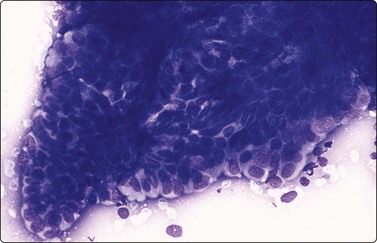

image

Fig. 13.6 Moderately-differentiated adenocarcinoma

Aggregate of malignant cells; marked nuclear enlargement and nuclear pleomorphism; nuclear crowding; microacinar pattern: indistinct cell borders. Note contrasting honeycomb sheet of benign epithelium (DQ, HP).

Moderately-differrentiated carcinoma (Figs 13.6, 13.7)

Microacini showing frank nuclear atypia,

Frequent obviously malignant irregular three-dimensional clusters,

Nuclear hyperchromasia,

Conspicuous nucleoli,

Some dissociated well-preserved malignant cells,

The smear may be overrun by malignant irregular three-dimensional clusters.

In smears of prostatic carcinoma, sheets of benign glandular epithelial cells are commonly seen side-by-side with aggregates of malignant cells (Fig. 13.6), reflecting the diffusely infiltrative growth of the tumor. Benign and malignant cells can be directly compared (very helpful clue) and differences in cytoarchitectural features are easily appreciated. Nuclear enlargement is one of the most important criteria of malignancy. Nucleolar enlargement is better demonstrated in Pap-stained smears.

Absence of visible cell membranes, nuclear crowding and overlapping and dissociation of cells are other important criteria. The presence of coarse intracytoplasmic secretory granules makes malignancy unlikely, but they can occasionally be found in cells from well-differentiated adenocarcinoma. Cytoplasmic vacuolation may be seen in both benign and malignant cells. Nuclear pleomorphism and chromatin abnormalities are obvious in less well-differentiated cancers but may be subtle in well-differentiated carcinomas, rendering a definitive malignant diagnosis difficult (Fig. 13.5). Demonstration of basal epithelial cells by immunocytochemistry may be of help in the distinction between well-differentiated adenocarcinoma and adenosis or basal cell hyperplasia,5 but interpretation is more difficult than in histologic sections. Immunostaining is a useful tool for the diagnosis of prostate cancer at metastatic sites.42 Results may be conflicting in metastases of poorly differentiated carcinomas.